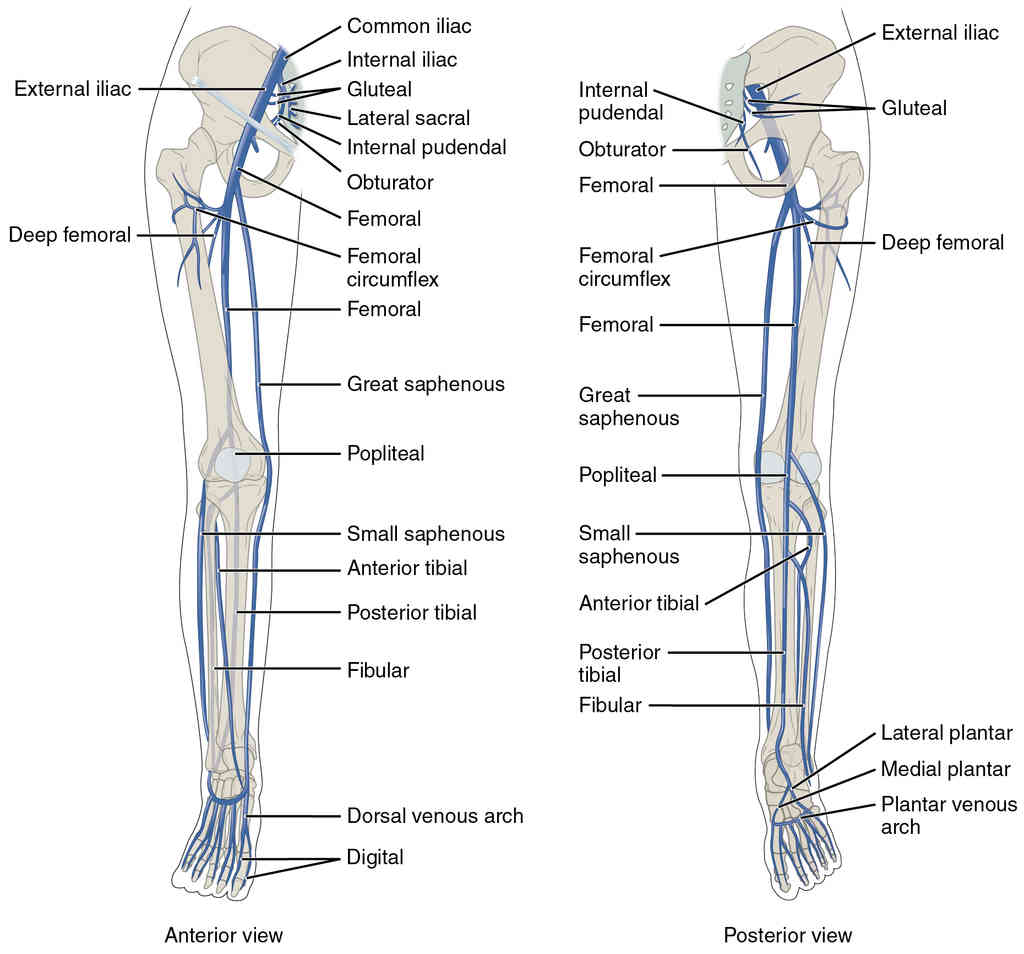

This page is under construction. For now, it is just a resource of the images found in the OpenStax Anatomy and Physiology Handbook. It wil slowly change into a revision tool. Each slide has a number. Use this to refer to the slide. When completed, it will have an unlabelled section, with labelled slides in parallel. On the unlabelled slides, write your answer and use the labelled slide to assess yourself. Keep track by also noting the number on each slide. Improvement at each attempt is important, more so than full marks on a first attempt.